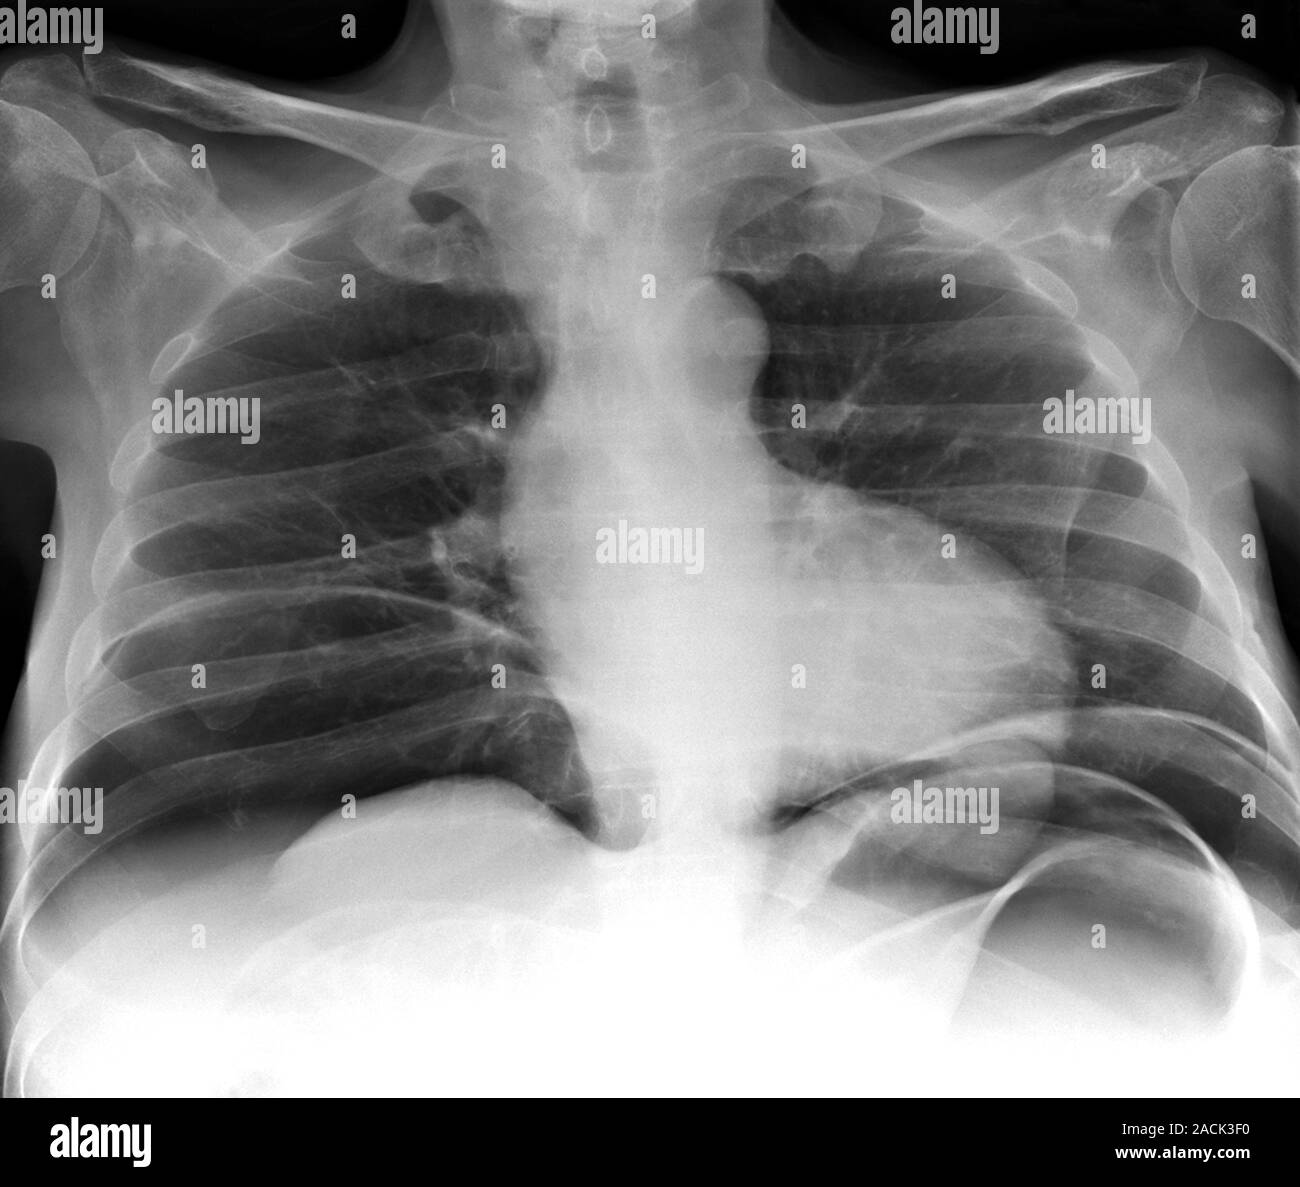

Abdominal air pockets. Chest Xray of a 44 year old patient showing air Air Pocket Stuck In Chest While the condition often resolves on its own,. a pneumomediastinum is a condition of air entering the chest. trapped gas can feel like a stabbing pain in your chest or abdomen. subcutaneous emphysema is a rare condition in which air becomes trapped under the skin. a person with air trapping in the lungs may feel short. Air Pocket Stuck In Chest.

From www.alamy.com

Abdominal air pockets. Frontal chest Xray of a 62yearold patient Air Pocket Stuck In Chest It often happens after an injury and causes chest pain. Swallowing too much air when you eat or drink can cause gas buildup in the chest area. a pneumothorax (collapsed lung) describes the condition in which air has become trapped next to a lung. The pain can be sharp enough to send you to the emergency room, thinking. . Air Pocket Stuck In Chest.